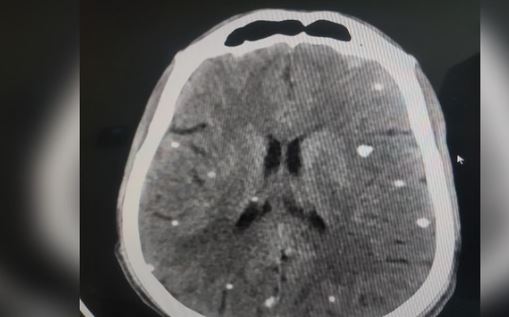

सिर में तेज दर्द, मिर्गी या अन्य तरह के दौरे, उल्टी, कमजोर नजर, पैरालिसिस, चक्कर आना, बार-बार बेहोश हो जाना, व्यवहार में बदलाव जैसे लक्षण दिखें तो तत्काल इसकी जांच कराएं। आपके दिमाग में कीड़े हो सकते हैं। बरेली के जिला अस्पताल की ओपीडी में इस तरह के लक्षण वाले मरीज पहुंच रहे हैं। जांच में न्यूरोसिस्टोसरकोसिस (एनसीसी) रोग की पुष्टि हो रही है। इस तरह के मरीजों की बढ़ती संख्या से चिकित्सक भी हैरत में हैं।